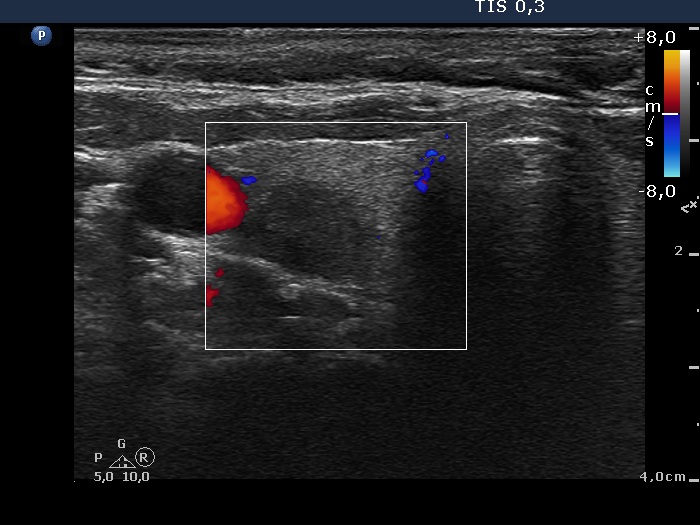

Extrathyroidal spread - case conp 045 (ultrasonographic picture 3)

Right lobe, transverse scan, color Doppler mode. The nodule displays no vascularization.